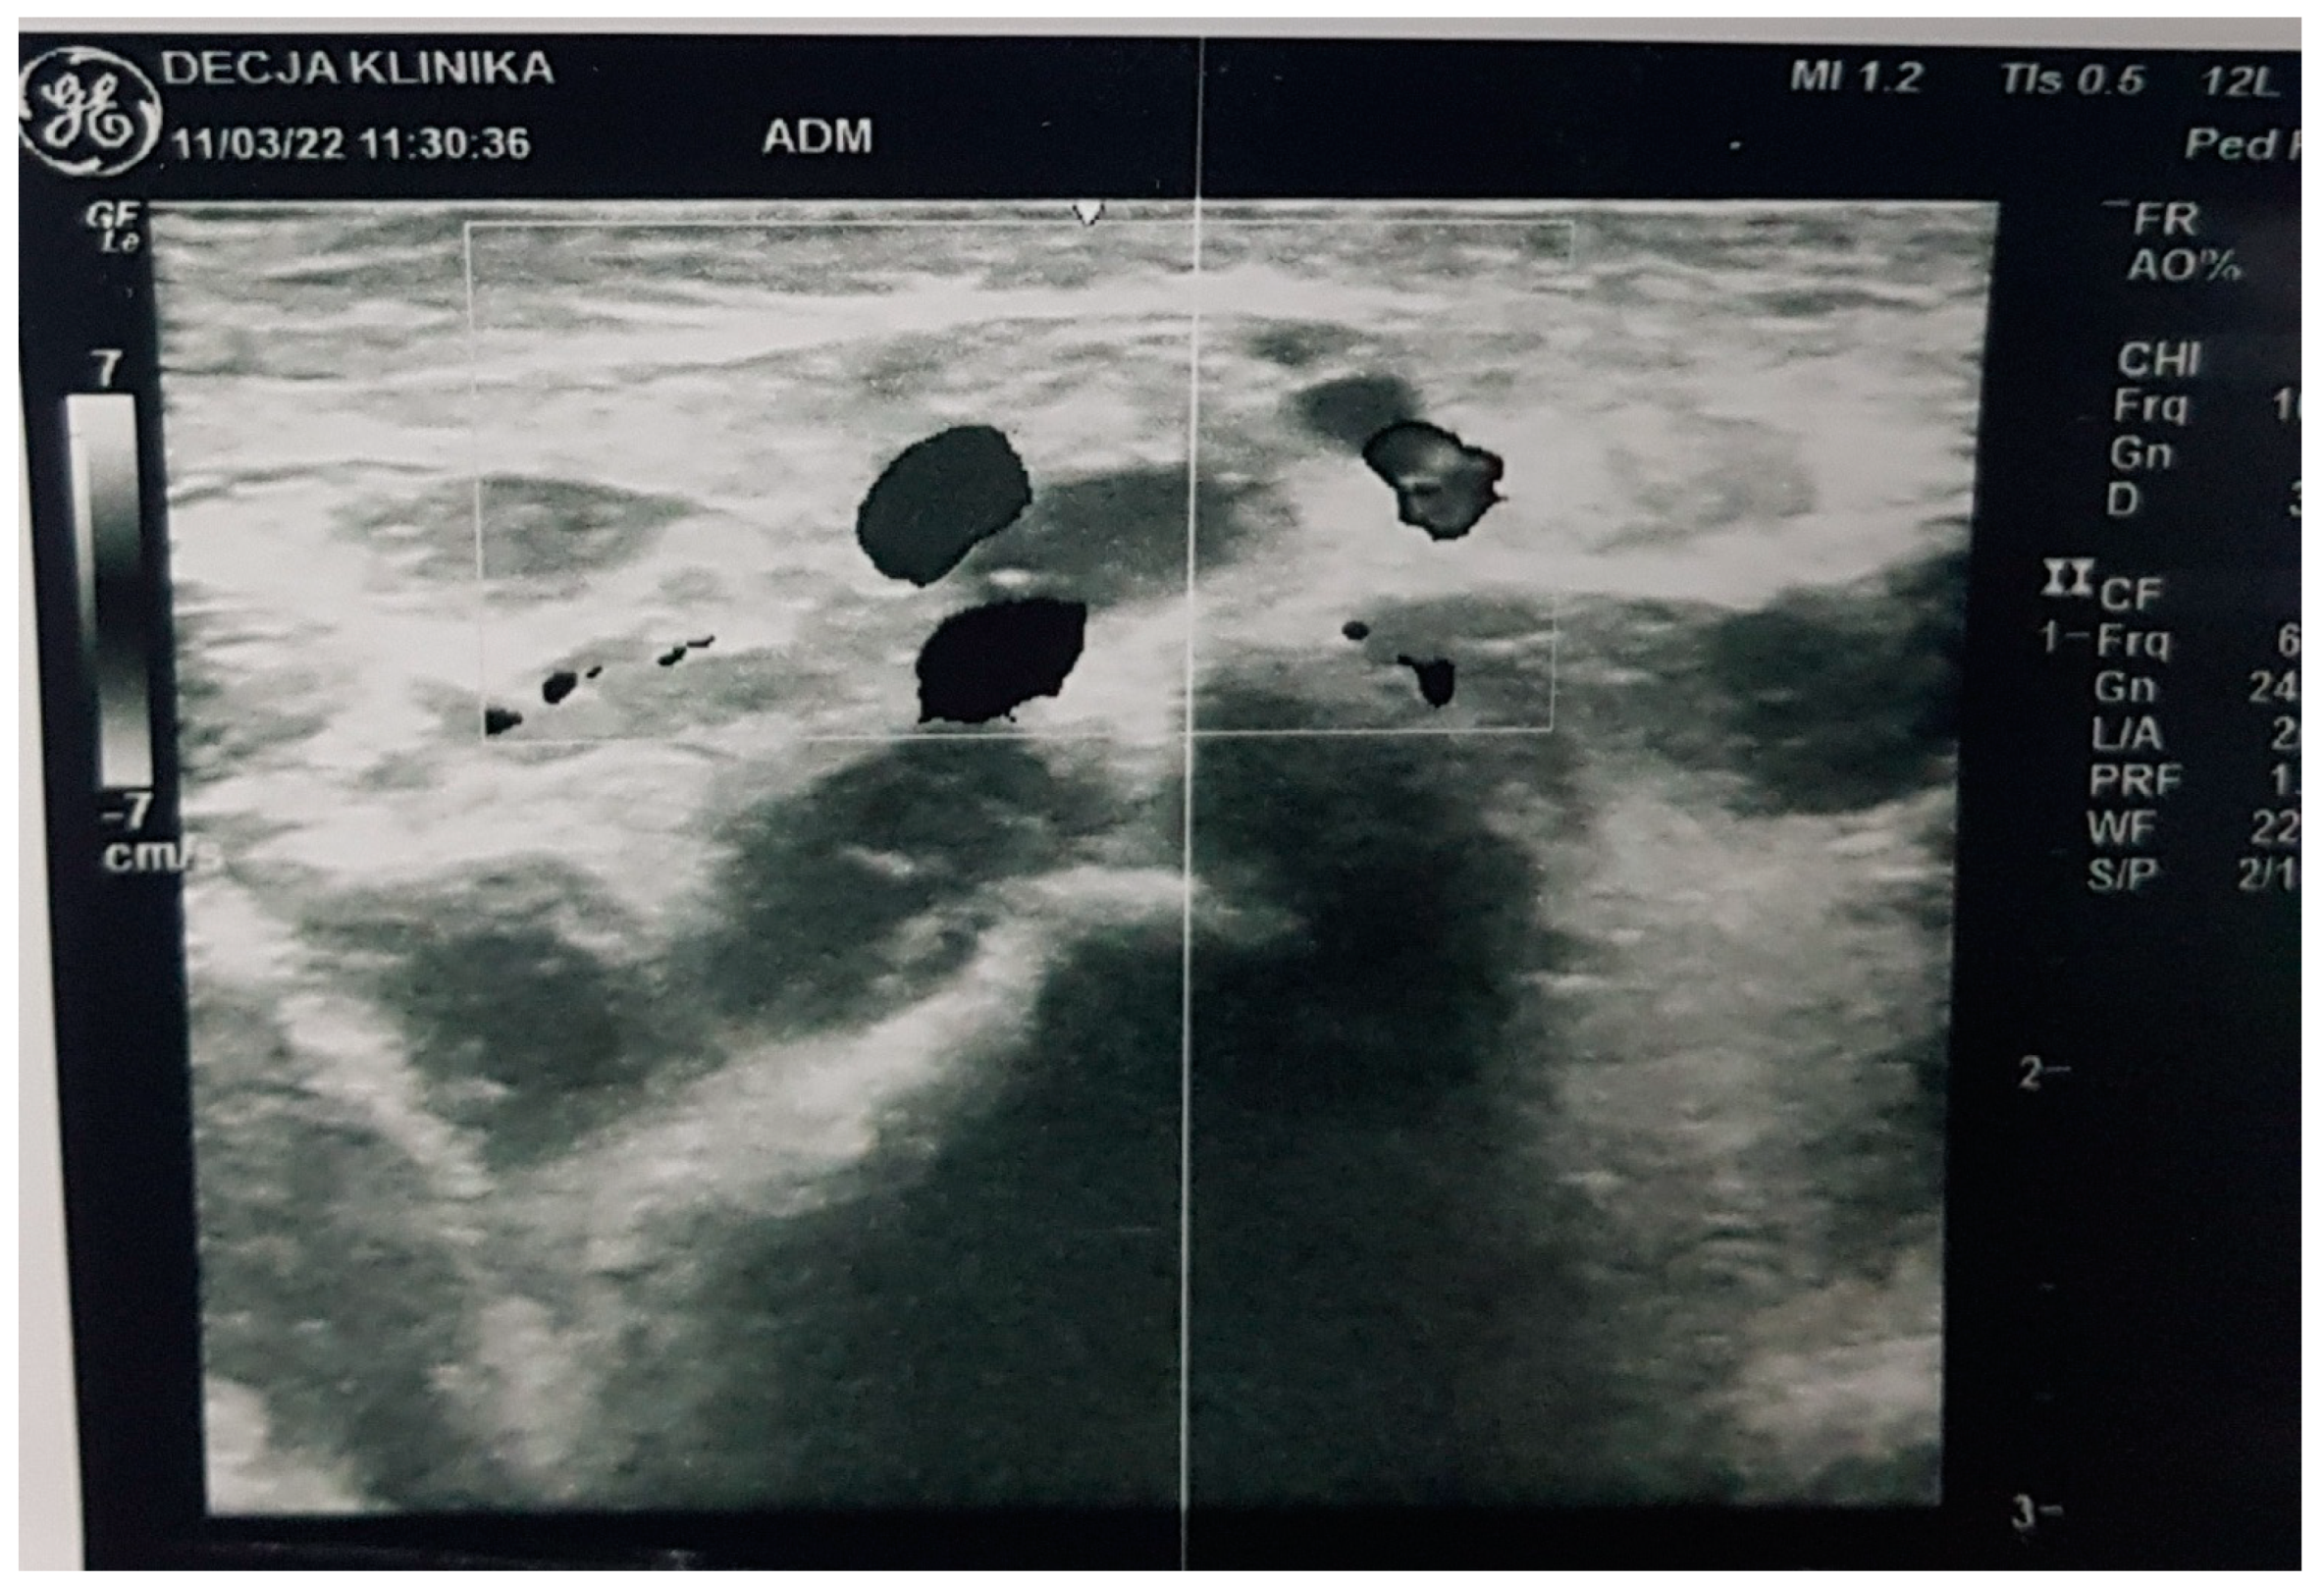

2. Commentary